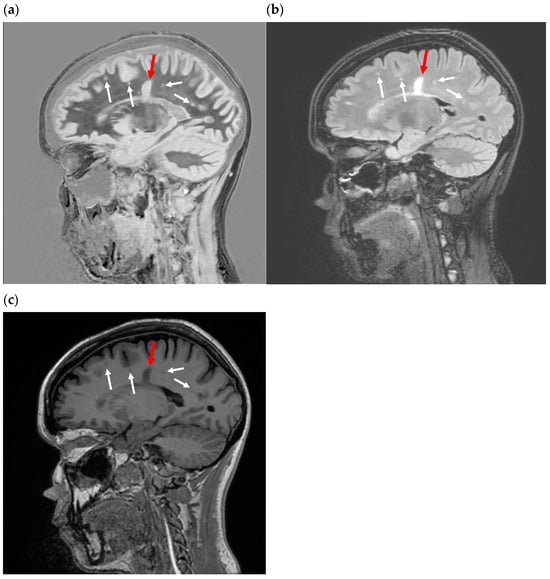

Figure 4.

Sagittal fast spin echo image of the brain with TR = 700 ms and TE = 10 ms. Gray matter (between the red arrows) is darker than the subcortical white matter (black asterix) and corpus callosum (yellow arrow). Fluid (white asterix) is even darker. This parallels the curve in Figure 2b.

Figure 5.

Inversion recovery T1 filter. (a) T1 tissue property filter for the IR sequence with TI = 1100 ms and TR = 5000 ms. Tissues with T1 = 1594 ms are nulled by these parameters. The slope of the curve in the region of most tissues of interest is negative, so that an increase in T1 results in a decreased signal. This produces an image like an SE T1-weighted image. The slope of the left half of the filter is steeper than the slope of the plot in Figure 2b, resulting in increased contrast. (b) Sagittal fast spin echo image of the brain with TR = 5000 ms and TE = 1000 ms. Gray matter (between the red arrows) is darker than the subcortical white matter (black asterix) and corpus callosum (yellow arrow). Fluid (white asterix) is even darker. This parallels the curve in (a). There is increased contrast compared to Figure 4, which reflects the larger difference in signal between gray and white matter in (a) than in Figure 2b.

The slope of Equation (8), with TR = 5000 ms and TI = 1000 ms at the T1 of white matter, is −8.2 × 10−4/ms. The sensitivity of the IR sequence to small changes in the T1 of white matter is therefore nearly twice that of the “T1-weighted” SE sequence (Table 1). A typical “T1-weighted” FSE-IR image of the brain is shown in Figure 5b.